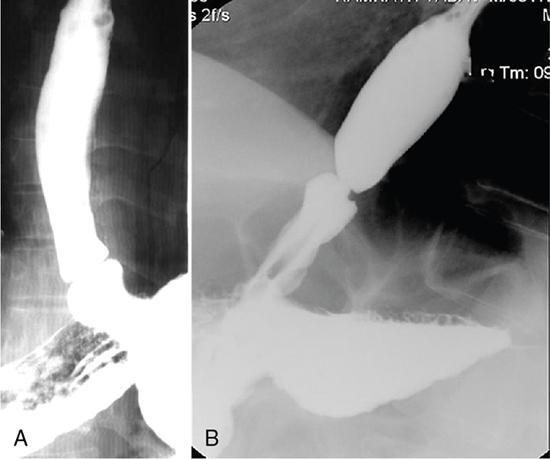

Gaurav Goswami, Gurdarshdeep Singh Madan, Ankita Dhawan Oesophagus is a fibromuscular tube responsible for conduction of food from oral cavity till the level of stomach. It is a hollow structure of approximately 25 cm. Proximal extent of oesophagus, that is cricopharynx begins at the level of C6 vertebral body. At this level, cricopharyngeus muscle merges with inferior constrictor muscle to form a functional zone known as upper oesophageal sphincter (UES). Oesophagus during its course through neck lies posterior to trachea and in thorax lies in posterior mediastinum. In mediastinum, oesophageal body courses to the left of the midline along left atrium, left main bronchus and aortic arch. It returns to the midline at level of T5. On plain radiograph, above T4 level, a sickle-shaped soft tissue shadow is seen overlying the tracheal air – where the trachea abuts the left lung – called the pleuroesophageal line. Similarly, azygoesophageal line is seen on the plain radiograph where the azygous vein and oesophagus abuts right lung (below T4 level). Oesophageal hiatus, present within right crus of diaphragm, is seen at the level of T10 vertebral body. Oesophagus through this hiatus enters the upper abdomen. An approximately 2–4 cm long segment of lower oesophagus is present in the hiatus. This segment shows asymmetrically arranged circular smooth muscles which forms the functional lower oesophageal sphincter (LES). This gastro-oesophageal junction is supported by various ligaments like phreno-oesophageal, gastrosplenic, phrenicolienal and gastrophrenic ligaments. These are responsible for strengthening of gastro-oesophageal junction. However, the most important phreno-oesophageal ligament (or membrane) is responsible for smooth longitudinal sliding of oesophagus through the diaphragmatic hiatus and it also acts as a demarcation between both thoracic and abdominal cavities. Oesophagus is thus anatomically divided into cervical, thoracic and abdominal parts. These parts have different arterial supply, venous supply and lymphatic drainage. Sensory, motor and parasympathetic fibres from vagus are responsible for nerve supply of all the parts of oesophagus. Vagal preganglionic nerve fibres in distal oesophagus are found to terminate within the Auerbach’s (myenteric) plexus. Similarly, Meissner’s plexus acts as a site for afferent impulses within the oesophageal wall. Structural relationship of oesophagus and its implications. These are depicted in Figure 8.1.1: For the purpose of staging of oesophageal cancer (AJCC), oesophagus is divided into upper, middle and lower parts on CT. Upper oesophagus comprises entire cervical oesophagus and thoracic oesophagus till the level of lower border of azygous vein, middle oesophagus from lower border of azygous vein till the lower border of inferior pulmonary vein and lower oesophagus from the lower border of inferior pulmonary vein to stomach including oesophago-gastric junction. The normal oesophageal wall is primarily made of four distinct layers, from inner to outer aspect: Oesophagus shows absence of serosa which is normally present in rest of the organs of GI tract. The distal oesophagus contains two rings – A ring and B ring (Schatzki’s ring) are seen at the proximal and distal to a mild fusiform dilatation of distal oesophagus called vestibule (Fig. 8.1.2). ‘A ring’ also known as muscular ring is present at the proximal extent of vestibule. It represents 4–5 mm band of hypertrophied muscle which can cause constriction at junction of vestibule and oesophageal lumen. It is normally lined by squamous epithelium. ‘A rings’ are rare seen. However, when symptomatic, they cause dysphagia to both solids and liquids. Symptomatic rings are treated endoscopically by dilators and botulinum toxin injection. ‘B ring’ is present at the distal end of the vestibule. It is relatively more common and in most cases seen in association with hiatus hernia. It is a thin membrane of squamous epithelium at its upper surface and columnar epithelium at lower surface. These rings comprise mucosa and submucosa. These rings can be congenital or acquired. Its relationship with GERD is documented. Usually these ‘B rings’ are asymptomatic but they can be symptomatic if they narrow oesophageal lumen to less than 13 mm. Symptomatic rings are treated with either bougie dilatation or mercury weight dilators. CLINICALLY RELEVANT EMBRYOLOGY OF OESOPHAGUS Gurdarshdeep Singh Madan Intrauterine life, especially the first 8 weeks, is extremely busy period in the development of the foetus. Any insult in this period will result in major congenital abnormality and a potentially fatal outcome. One should be mindful of the fact that different anatomically structures are developing simultaneously and not sequentially. Therefore, a specific teratogenic insult caused by drugs/radiation or IU infection like virus results in manifestations in more than one organ system. Over the course of this chapter, we will try to make embryology of oesophagus simple to understand and relate it to the simultaneous development of the respiratory system and embryonal arterial arches and also briefly mentioning their clinical relevance. At around 4th week of intrauterine life, a primordial gut is formed by the invagination of the dorsal yolk sac by lateral embryonal folds and folding of the head and the tail ends. Initially, the gut is a closed tube with oropharyngeal membrane at the cranial end and the cloacal membrane at the caudal end. The oropharyngeal membrane ruptures and orifice is formed around the 26th day. The cranial third of this alimentary system is called the ‘foregut’ (see Fig 8.1.3). Immediately following the formation of the primordial gut, a medial outgrowth develops caudal to the four pair of pharyngeal arches – known as the Laryngo-tracheal groove. By end of the first month (4th week) of intrauterine life, the laryngo-tracheal groove lengthen and protrudes caudally to form laryngo-tracheal diverticulum (LTD). The caudal end of LTD enlarges to form a ‘single’ globular respiratory bud from which both lungs develop. Simultaneously, the longitudinal tracheo-esophageal folds begin to form and start invaginating towards each other. By the end of the 5th week, the tracheo-esophageal folds fuse to form a complete partition, dividing the primitive foregut into ventral laryngo-tracheal tube and dorsal primordial pharynx and oesophagus. The laryngo-tracheal tube opens into the pharynx through a small opening known as the primordial laryngeal inlet (see Fig 8.1.4). Initially after its formation, the length of oesophagus is very short relatively as compared to the total length of primordial gut. However, the oesophagus elongates rapidly as compared to rest of the gut to attain postnatal relative length by the 7th week. During this time, the lumen of oesophagus is obliterated by proliferating epithelium and mucosal glands, which are derivatives of the endoderm. The recanalization of oesophagus is completed by end of the 8th week. The muscles of oesophagus are striated in superior third and derived from the mesenchyme of the fourth and the sixth pharyngeal arches. (Note: Fifth pharyngeal arch disappears.) The inferior third of oesophagus has smooth muscles developed from the splanchnic mesenchyme. The mid third of the oesophagus shows gradual change from striated to smooth muscles. The change from striated to smooth muscles in the oesophageal wall roughly corresponds to the level of arch of aorta in an adult. It must also be noted that both striated and smooth muscles of oesophagus are supplied by the vagus nerve (CN X) which is the nerve of fourth and sixth pharyngeal arches. The chart below illustrates the simultaneous development of pharyngeal arches, respiratory and alimentary system and briefly outlines the development of arterial tree (see Flowchart 8.1.1). The schematic diagram of the embryonal basis of congenital oesophageal abnormalities is attached below. The details of congenital anomalies are covered in relevant chapters (see Flowchart 8.1.2). IMAGING TECHNIQUES – OESOPHAGUS Gurdarshdeep Singh Madan Oesophagus like most other organs of the body may develop ailments – both benign and malignant. They may be congenital, presenting in neonatal period or later in life. The diseases may be structural affecting mucosa; they may also spare the mucosa or could be a transient motility disorder. Hence, the investigation chosen should have maximum cost-benefit to the patient as well as present minimum risk to the patient with judicial use of radiation. With advent of upper gastrointestinal endoscopy, it has replaced radiological studies as preferred investigation for multiple presentations. However, the utility of the radiological studies cannot be discounted due to their ability to provide information regarding motility as in upper gastrointestinal contrast studies and cross-sectional data for cancer staging. During the course of this chapter, we will discuss in brief various imaging modalities and techniques. Though endoscopy has largely displaced imaging studies as initial investigation of choice for dysphagia, their role in motility disorders is limited. Endoscopic ultrasound is investigation of choice for evaluating T1 and T2 oesophageal Ca. PET-CT is functional imaging which is gold standard in evaluating distant metastasis. CT scan is initial staging investigation for T3 and T4 disease and provides valuable information in preoperative planning and postoperative assessment. Contrast oesophagogram done with correct technique is an important investigation for evaluation of motility disorder and is a competent investigation in evaluation of structural/mucosal disorders. The choice of the imaging modality to evaluate a patient depends on patients’ condition, clinical suspicion and the risk benefit ratio to the patient. In a resource constraint setting, availability and affordability of the investigation is also equally important. Many international societies have propounded the guidelines for first investigation of choice. American College of Radiology appropriateness criteria (ACR-AC) for imaging studies in evaluation dysphagia has been adapted as Table 8.1.1. The investigation of choice in other clinical settings are covered in the respective chapters. Fluoroscopic biphasic oesophagogram Fluoroscopic single contrast oesophagogram Oesophageal transit nuclear medicine scan Fluoroscopic modified barium swallow CT neck and chest with or/and without IV contrast Fluoroscopy pharynx dynamic and static imaging Fluoroscopic biphasic oesophagogram Fluoroscopic single contrast oesophagogram Fluoroscopic modified barium swallow Oesophageal transit nuclear medicine scan CT neck and chest with or/and without IV contrast Fluoroscopy pharynx dynamic and static imaging Fluoroscopic single contrast oesophagogram CT neck and chest with IV contrast CT neck and chest without IV contrast Oesophageal transit nuclear medicine scan CT neck and chest with and without IV contrast Fluoroscopy pharynx dynamic and static imaging Fluoroscopic modified barium swallow CT neck and chest with IV contrast Fluoroscopic single contrast oesophagogram Fluoroscopic modified barium swallow Fluoroscopic biphasic oesophagogram Oesophageal transit nuclear medicine scan CT neck and chest with or/and without IV contrast Fluoroscopy pharynx dynamic and static imaging Mazzeo et al. and Carrascosa et al. have described technique of virtual oesophageal endoscopy with use of air insufflation via catheter inserted into the upper oesophagus and by use of effervescent agents like those used in fluoroscopic oesophagogram. However, despite these technological assessments, the sensitivity of CT scan in identifying T1 and T2 disease is limited. The CT scan is also limited in identifying normal-sized metastatic lymph node. The limitation can only be partially addressed by using morphological appearance like extracapsular spread and central necrosis. National Comprehensive Cancer Network (NCCN) guidelines for oesophageal and oesophagogastric Ca recommends CECT chest and abdomen with oral and IV contrast in staging assessment of cancers T3 and above. CT is indicated in assessment of early and delayed postoperative complications. Lantos et al. and Upponi et al. have demonstrated slightly better sensitivity of CT in detecting early postoperative complications. However, it is marred by poor specificity in the same period. In delayed postoperative dysphagia, use of CT oesophagogram has demonstrated increase in sensitivity in identifying recurrent disease, abnormality caused by surgical hardware/technique or a late onset seroma. CT oesophagogram (Table 8.1.3) can be performed by preparing 3% iodinated contrast in water or thickening agent like Simply Thick to form a honey- or nectar-like consistency swallowed on the table with last gulp taken immediately prior to the acquisition. The images are reconstructed in curved multiplanar reformats in soft tissue window. MRI and MR oesophagogram – Quint et al. was the first, however, unsuccessful attempt evaluation of oesophagus on a 0.35T MRI, 35 years back. Since then, there has been substantial advancement in the MRI technology with evolution of quicker and dynamic sequences, and advancement of k space filling technology leads to further shortening of scan times. Yamada et al. used MRI in vitro staging of Ca oesophagus with 4.7 T MRI in 1997. Subsequently, high-field MRI up to 7T have been used in evaluation oesophageal specimen and advanced MRI imaging techniques like diffusion tensor MRI and tractography have been used. In spite of these advancement in evaluation of ex vivo specimen, the advancement and utilization of MRI for clinical purposes has been gradual and sparse. In 2005, Riddell et al. used surface coil MRI in staging of oesophageal carcinoma. Sakurada et al. showed promising results in staging of T3 and T4 Ca oesophagus patients using T2WI and DWI. Over the recent years, the advancements in in vivo MRI of oesophageal Ca have been focused on identification of lymph nodal involvement (Alper et al.), staging postconcurrent radio-chemotherapy (Wang et al.), postoperative nodal recurrence (Shuto et al.) and gross tumour volume delineation (Hou et al.). Pavone et al. (1992) used Gadopentetate dimeglumine – barium paste in distending and opacifying and assessment of concentric/eccentric tumour growth in patients of Ca oesophagus and identifying a case of oesophageal leiomyoma in their study. In 1996, Ogawa et al. used ferric ammonium citrate-cellulose paste for oesophageal lumen opacification with excellent luminal opacification in 84% of the sagittal images and 79% of the axial images. Subsequently, Zhang et al. (2012) utilized high T2* signal of water to provide good contrast in MR oesophagogram. For easy intake of water, the head of patients was padded slightly high and water swallowing was done through a pipe/straw and patients were instructed to swallow the water continuously during the acquisition. Without respiratory triggering, sagittal and axial True fast imaging with steady state procession (True FISP) T2*weighted images were obtained. The diagnostic quality of water swallow was graded excellent in 97.7% of the sagittal images and in 81.8% of the axial images the cases. Even after the advances elucidated above, the present utility of MRI in diagnosis of oesophageal disease is more as an occasional adjunct for resolving specific clinical dilemmas rather than as a primary investigation. However, the future of the modality is bright and promising with continuous improvement in acquisition technology and the hardware. EUS is a specialized endoscope with an ultrasonographic probe to evaluate hollow visceral organs. It is useful to visualize oesophagus and stomach lining. Adjacent organs can also be visualized like liver, pancreas, GB, para-aortic region and mediastinum. EUS is done under mild sedation. EUS is available in two types of probes, that is Linear and Radial Probe. Gastrointestinal tract is visible in a healthy patient as five layers. These are first layer – superficial mucosa, second – mucosal, third – submucosal, fourth – muscularis propria and fifth – oesophageal adventitia. EUS is helpful mainly in characterizing the lesion as benign or malignant. On a standard endoscopy study, these lesions are usually seen as a bulge within wall. EUS helps in determining the location of lesion, whether it is within wall or outside the wall. Also it helps in determining the extent of involvement of lesion and its relationship with surrounding structures. It also has a role in looking for secondary causes of motility disorder like achalasia. However, its diagnostic as well as therapeutic role in oesophageal cancer is noteworthy. Endoscopic ultrasound plays a vital role in local staging of oesophageal cancer. Staging of oesophageal cancer is essential to choose appropriate therapy. Surgery is the gold standard for staging of oesophageal cancer. Usually in clinical practice, most patients undergo preoperative therapy as chemoradiation which is followed by surgery. Thus, for pretreatment staging, EUS findings are complementary with radiological imaging like MRI, CT scan and PET scan. Standard protocol is to perform EUS in most cases of oesophageal cancer. EUS is useful in early stages of oesophageal cancer, that is T1a and T1b. It is helpful in evaluating lymph node enlargement. Whenever a patient is assessed for feasibility of early cancer for mucosal resection via endoscopic procedure, it is important to rule out deeper tissue invasion and lymph node metastasis. EUS also plays essential role in lymph node FNA and biopsy in doubtful lesions. Role of EUS in advanced oesophageal cancer is limited. Usually EUS cannot be used to differentiate between T3 and T4. Distant metastasis is usually well diagnosed on cross-sectional imaging. EUS can only detect invasion into aorta as T4 which is better visualized in CT scan. EUS has limitations like it cannot look into metastases where CT scan and PET scan are useful. Role of EUS in postradiation or chemotherapy is under evaluation. EUS is technically difficult and has a significant learning curve. ALGORITHMIC APPROACH TO A PATIENT WITH OESOPHAGEAL DYSPHAGIA Gurdarshdeep Singh Madan, Ankita Dhawan Swallowing is essential not only for maintaining the nutrition for life but also a major determinant in one of the pleasures of life. The voluntary component of swallowing is the initial 10% and is initiated by collecting the food bolus onto the tongue and voluntarily propelling the bolus into the oropharynx. This initiates a wave of involuntary contraction and relaxation of pharyngeal muscles which pushes the food through cricopharynx into the oesophagus. Closure of glottis and cessation of respiration are reflex activities. Thereafter, the ‘peristaltic’ ring of oesophageal muscle contraction pushes the food towards the stomach at a rate of approximately 3.0–4.5 cm/s. The semisolid and liquid food falls by gravity, ahead of the peristaltic wave when the individual is upright. In cases where there is incomplete clearing of the oesophagus, secondary peristaltic waves are generated which are weaker than the primary peristaltic wave and aid in clearing the oesophagus. Unlike the rest of oesophagus, lower oesophageal sphincter (LES) is contracted at rest and relaxes on swallowing, which prevents reflux of gastric contents into the stomach while permitting the food bolus into the stomach (Fig. 8.1.7). Difficulty in swallowing is a common problem affecting approximately 3%–15% of general population. This prevalence increases in elderly population and in patients with other comorbidities. Understanding the symptomatology and pathophysiology of dysphagia is essential for the radiologist to plan the correct investigation and to remain clinically relevant in management of the patient. The symptoms of difficulty on swallowing has been further classified into various terminology, each highlighting a specific association and hence clinically leading to a smaller set of differential diagnosis (Table 8.1.4). Depending on location, dysphagia may be localized to oral, oro-pharyngeal or oesophageal regions. Dysphagia can also be subclassified as Structural dysphagia – caused by mismatch between the size of food bolus and the lumen of the aerodigestive track/oesophagus that is a large food bolus or the narrow lumen. It is classically described as difficulty in swallowing solid food. Motor dysphagia – it is caused by abnormalities of peristalsis/impaired upper oesophageal sphincter relaxation/closure and impaired lower oesophageal sphincter relaxation. It is difficulty in swallowing both solid and liquid foods. There are certain limitations to such generalization of symptoms. For example, Scleroderma, which is primarily an oesophageal motility disorder, presents initially with mild dysphagia on swallowing solid bolus. Also, in patients with oropharyngeal structural pathology, patient may be more symptomatic and concerned due to inability to handle fluids and causing aspiration. In other subset of patients, more than one mechanism may be responsible causing both improper propulsion of food and associated secondary luminal narrowing by stricture formation. Odynophagia generally arises due to passage of bolus along inflamed or ulcerated mucosa causing irritation, which may be due to foreign body ingestion, infective, chemical or inflammatory oesophagitis. Associated symptoms like cranial nerve abnormalities, hoarseness and other general and systemic symptoms and signs may point towards the location and cause of dysphagia. The patient may be able to localize the location of dysphagia. However, the sensation of dysphagia in oesophagus (especially in distal two-thirds) may be proximally referred in a third of the cases. Inability to produce sufficient saliva (Xerostomia) may also be perceived as dysphagia, especially common in elderly (see Fig. 8.1.8). Adult oesophagus measures approximately 17–26 cm in length and extend from cricopharynx to the lower oesophageal sphincter. Oesophagus can be anatomically divided into cervical oesophagus (cricopharynx to suprasternal notch) and thoracic oesophagus. The structural causes of the dysphagia manifest when the lumen of the oesophagus has been reduced to one-third (~13 mm in size). Dysphagia in a setting of Gastro-oesophageal Reflux Disease is very common and is multifactorial in pathophysiology – increased mucosal sensitivity, impaired distensibility and motor function, formation of strictures. Propulsive/motor disorders can be due to abnormality of peristalsis (both excessive and reduced) or relaxation of lower oesophageal sphincter (see Figs. 8.1.9–8.1.13). Few common causes of oesophageal dysphagia are enumerated below: Presentation and causes of dysphagia in neonates and infants tend to be different from adults. They may present as aspirations, incessant crying in addition to choking and inability to feed. In neonates, the causes may be neuromuscular or central in origin affecting swallowing or could be congenital in nature affecting oral or pharyngoesophageal phase of swallowing (Fig. 8.1.14). In older children and toddlers, ingestion of foreign body is one of the most common cause of dysphagia/choking. In these cases endoscopy is therapeutic. Ingestion of caustic agents can cause severe caustic oesophagitis which can be potentially fatal. In children, high index of suspicion should be present and relevant history for ingestion of caustic agents should be elicited. Other causes of dysphagia (Fig. 8.1.15) in paediatric age group are covered in detail in relevant chapters. Which investigation to choose: The armamentarium available for a clinician while evaluating dysphagia are mentioned below: Before the advent of flexible upper gastrointestinal endoscopic techniques, contrast (barium) upper gastrointestinal radiological studies especially barium swallow were the cornerstone in evaluating dysphagia. However, endoscopic examination of the oesophagus is presently the first line investigation of choice for oesophageal dysphagia. Endoscopy offers the advantage of mucosal assessment and characterization, ability to identify Barrett’s metaplasia and offer diagnostic and therapeutic interventions in a single sitting. Endoscopy is relatively deficient in diagnosing motility disorders and identifying benign conditions which cause dysphagia but do not cause mucosal abnormalities. Barium swallow should be done as a first line investigation of choice where dysmotility or oesophageal ring/webs/subtle strictures are suspected. A well-planned barium study with barium-coated appropriate bolus such as bread/marshmallow/barium pill may demonstrate oesophageal ring causing hold up of contrast. Barium swallow is also the first line investigation of choice for Achalasia. It may also be used for characterization of hiatal hernia. Oesophageal manometry/HRIM (high resolution impedance manometry) is specifically done in patients in whom endoscopy and barium studies are noncontributory. They show high pressure at upper and lower oesophageal sphincter with mid oesophagus showing waves of peristalsis. It is the gold standard to diagnose achalasia with certainty. It is also of immense value in diffuse oesophageal spasm and nutcracker oesophagus. Endoscopic ultrasound combines the advantage of an endoscope with high-frequency ultrasound, providing improved spatial resolution, which is useful for staging of oesophageal carcinoma and allows taking directed biopsies for histopathology. It can also be used to assess Barrett’s metaplasia and evaluating other submucosal tumours/paraoesophageal lymph nodes. PET-CT scan is a preferred modality of oesophageal and oesophago-gastric junction Ca and includes PET CT from skull base to mid-thigh in absence of M1 disease. Early disease may not be detectable on PET-CT as depth of invasion cannot be accurately assessed. Assessment of locoregional lymph node is limited as uptake from oesophageal lesion cannot be differentiated from uptake from periesophageal lymph nodes due to limited spatial resolution of PET. Nonregional or distant lymph node involvement can be well identified and assist in accurately upstaging and planning treatment of Ca oesophagus. CT scan has limited value in identifying early oesophageal Ca and identifying nonregional lymph nodes. It can be used in assessing recurrence and to check for integrity postoesophagectomy. Ambulatory reflux monitoring is useful in diagnosing GERD without oesophagitis. Endoscopy is normal in these patients with hypersensitive oesophageal mucosa – causing pain. The electrode tip is placed in distal oesophagus and pH is measured over 24/48 hours. The outcome is expressed as percentage duration when the distal oesophageal pH was less than 4. This can be combined with impedance monitoring to increase sensitivity. They also serve as a guide to evaluate poor response to therapy for GERD. A reading of more than 6% is considered abnormal. Additional newer advances like use of Functional Lumen Imaging Probe (FLIP) has been evaluated to assess oesophagogastric junction distensibility and distension-mediated peristalsis in oesophageal motility disorders. The investigations are often guided by clinician’s preferences, availability of the investigation and likelihood of a probable diagnosis on history taking and clinical examination. OESOPHAGEAL MOTILITY DISORDERS Ankita Dhawan Oesophagus is around 25–40 cm muscular tube in posterior mediastinum. It comprises both striated and smooth muscles. It extends from the level of upper oesophageal sphincter (UES – at the level of cricopharyngeal muscle) and lower down till the level of lower oesophageal sphincter (LES – present at the junction of lower end of oesophagus and cardia of stomach). Normal function of oesophagus is to transport both solids and liquids to stomach, which is mainly attributed to oesophageal peristalsis and gravitational force. Therefore, radiographic evaluation of oesophageal peristalsis is done in recumbent position to remove the contribution from gravity.